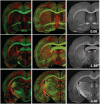

Diffusion tensor imaging is highly sensitive to the microstructural integrity of the brain and has uncovered significant abnormalities following traumatic brain injury not appreciated through other methods. It is hoped that this increased sensitivity will aid in the detection and prognostication in patients with traumatic injury. However, the pathological substrates of such changes are poorly understood. Specifically, decreases in fractional anisotropy derived from diffusion tensor imaging are consistent with axonal injury, myelin injury or both in white matter fibres. In contrast, in both humans and animal models, increases in fractional anisotropy have been suggested to reflect axonal regeneration and plasticity, but the direct histological evidence for such changes remains tenuous. We developed a method to quantify the anisotropy of stained histological sections using Fourier analysis, and applied the method to a rat controlled cortical impact model to identify the specific pathological features that give rise to the diffusion tensor imaging changes in subacute to chronic traumatic brain injury. A multiple linear regression was performed to relate the histological measurements to the measured diffusion tensor changes. The results show that anisotropy was significantly increased (P < 0.001) in the perilesioned cortex following injury. Cortical anisotropy was independently associated (standardized β = 0.62, P = 0.04) with the coherent organization of reactive astrocytes (i.e. gliosis) and was not attributed to axons. By comparison, a decrease in white matter anisotropy (P < 0.001) was significantly related to demyelination (β = 0.75, P = 0.0015) and to a lesser extent, axonal degeneration (β = -0.48, P = 0.043). Gliosis within the lesioned cortex also influenced diffusion tensor tractography, highlighting the fact that spurious tracts in the injured brain may not necessarily reflect continuous axons and may instead depict glial scarring. The current study demonstrates a novel method to relate pathology to diffusion tensor imaging findings, elucidates the underlying mechanisms of anisotropy changes following traumatic brain injury and significantly impacts the clinical interpretation of diffusion tensor imaging findings in the injured brain.